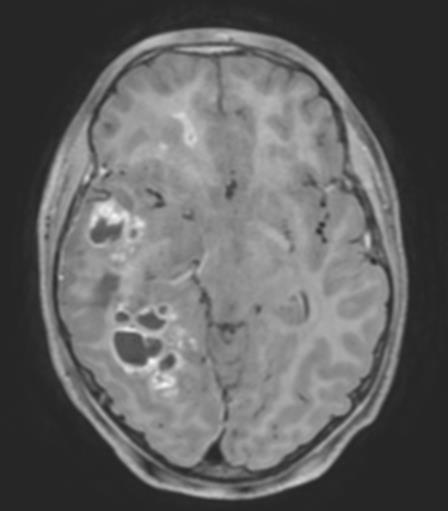

FIGUR 1: MR-bildene viser tydelig heterogenitet i hjernesvulster hos barn. A – Pilocytisk astrocytom i synsnerve (WHO grad ­1); B – Diffust astrocytom (WHO grad – 2); C – Høygradig gliom (WHO grad – 4); D – Diffust midtlinjegliom (WHO grad – 4); E ­ Dysembryoplastisk nevroepitelial tumor (WHO grad – 1); F – Gangliogliom (WHO grad – 1); G – Supratentorielt ependymom (WHO grad – 3); H – Pilocytisk astrocytom (WHO Grad – 1); I – Medulloblastom ( WHO grad – 4); J – Medulloblastom (WHO grad – 4); K – Ependymom ( WHO grad – 4); L ­ Glionevronaltumor forenlig med RGNT ( WHO – Grad 1). Alle pasienter har samtykket til bruk av bildene.